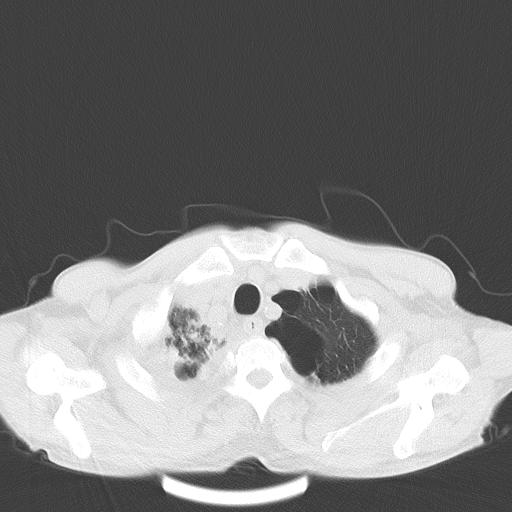

男性 75  咳嗽 一周前发热最高达39

右肺继发型tb并右侧tb性胸腔炎,右侧胸腔大量积液并右下肺膨胀不全,慢支肺气肿、多发肺大泡。建议抽胸水实验室检查并复查排除恶性在占位。

右上肺继发型肺结核,右胸腔中等量积液。

左上肺大泡。

结核的基础上有纵隔淋巴结肿大,右侧有胸水,但右侧纵隔反而窄,说明有肺有不张。

再就是右下肺有块影,和不张混合,还是不能除外肺癌。

补充材料,患者2月份ct片大致正常,双侧胸腔积液,2月份抽胸水未发现ca细胞,现患者发热,痰多,各气管通畅,

1)右肺继发型肺结核。2)左肺胸膜下多发性肺大泡。3)右侧胸腔积液。